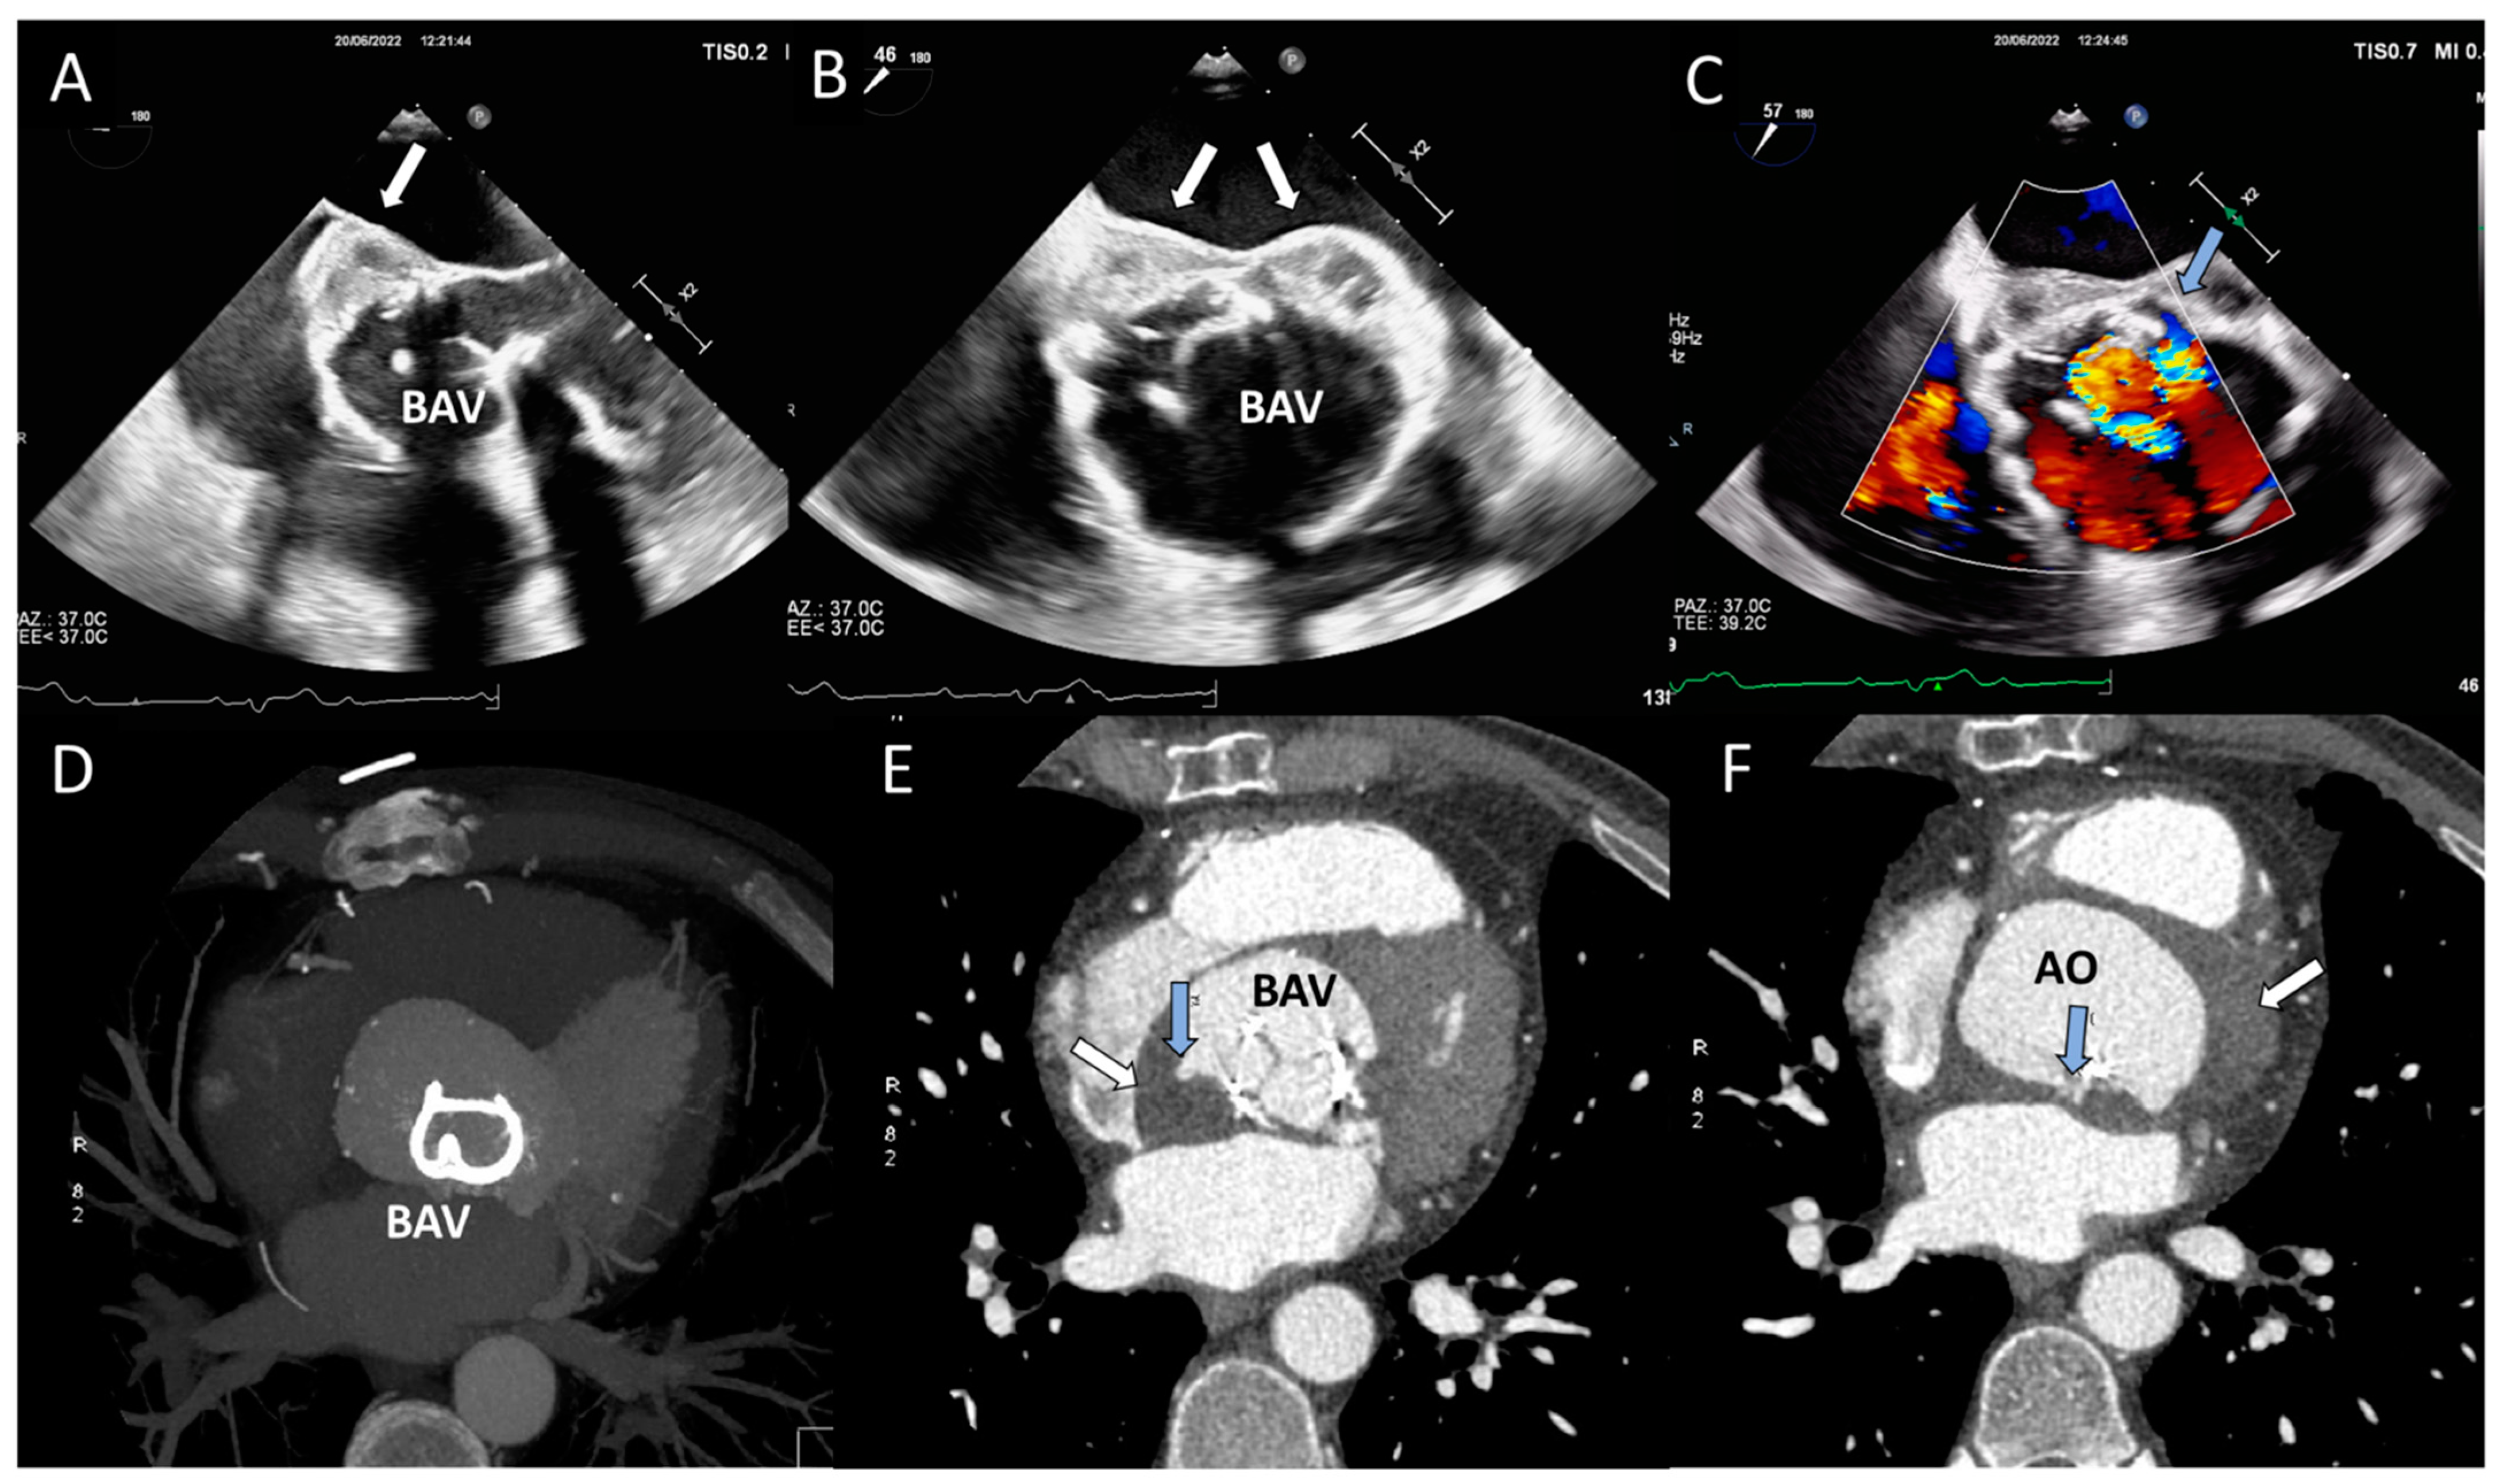

Figure 11. Periprosthetic abscess and detachment in a patient with bioprosthetic aortic valve. (A,B) Transesophageal echocardiogram in mid-esophageal view showing iso-hypoechoic space posteriorly to the bioprosthetic aortic valve (BAV). (C) Transesophageal echocardiogram in mid-esophageal view, with color Doppler showing paravalvular posterior leak and regurgitation (light blue arrow). (D) Contrast CT 3D volume rendering: The struts of the BAV are hyperdense and clearly visible. (E,F) The abscess (white arrow) appears like an isodense region posterior to the BAV; the light blue arrow indicates the presence of multiple leaks with contrast inside.